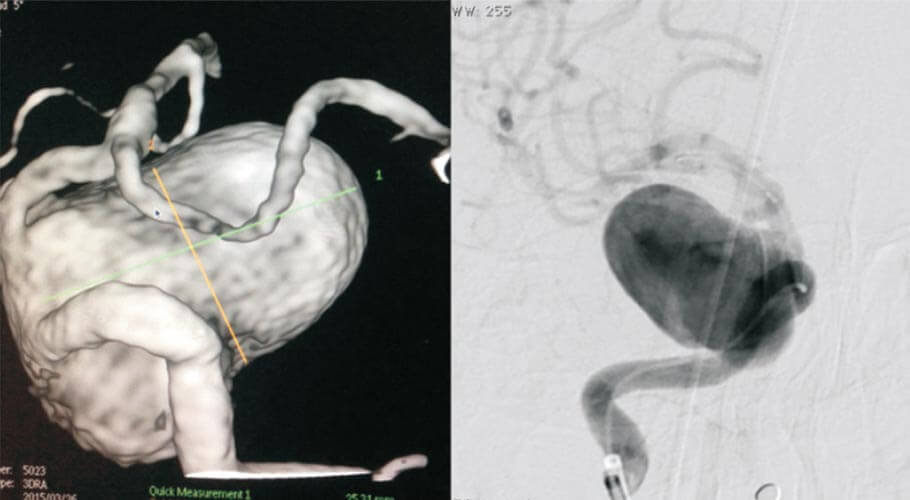

The incidence of cerebral aneurysms in general population is between 2-4 per 1000. Rupture of the aneurysms presents as subarachnoid haemorrhage which manifests as thunderclap headache. Aneurysms if large enough can also present with mass effect in the form of cranial nerve palsies, focal neurological deficits and headache. Aneurysms , sometimes are incidentally detected on imaging studies like CT angiography or MR angiography. Aneurysmal clipping by microsurgery has been the uniform traditional treatment before the advent of detachable GDC coils. The detachable coil technology, invented by Guglielmi- a French interventionist, makes selective occlusion of the aneurysm feasible by precise placement of the coils into the aneurysm, while preserving the normal parent artery.

Aneurysm endovascular treatment is further advanced by invention of hyper compliant ballons and stents, which are helpful in the treatment of complex wide necked aneurysm. Flow diversion stents occlude the aneurysm by flow remodelling away from the aneurysm rather than by endoluminal methods